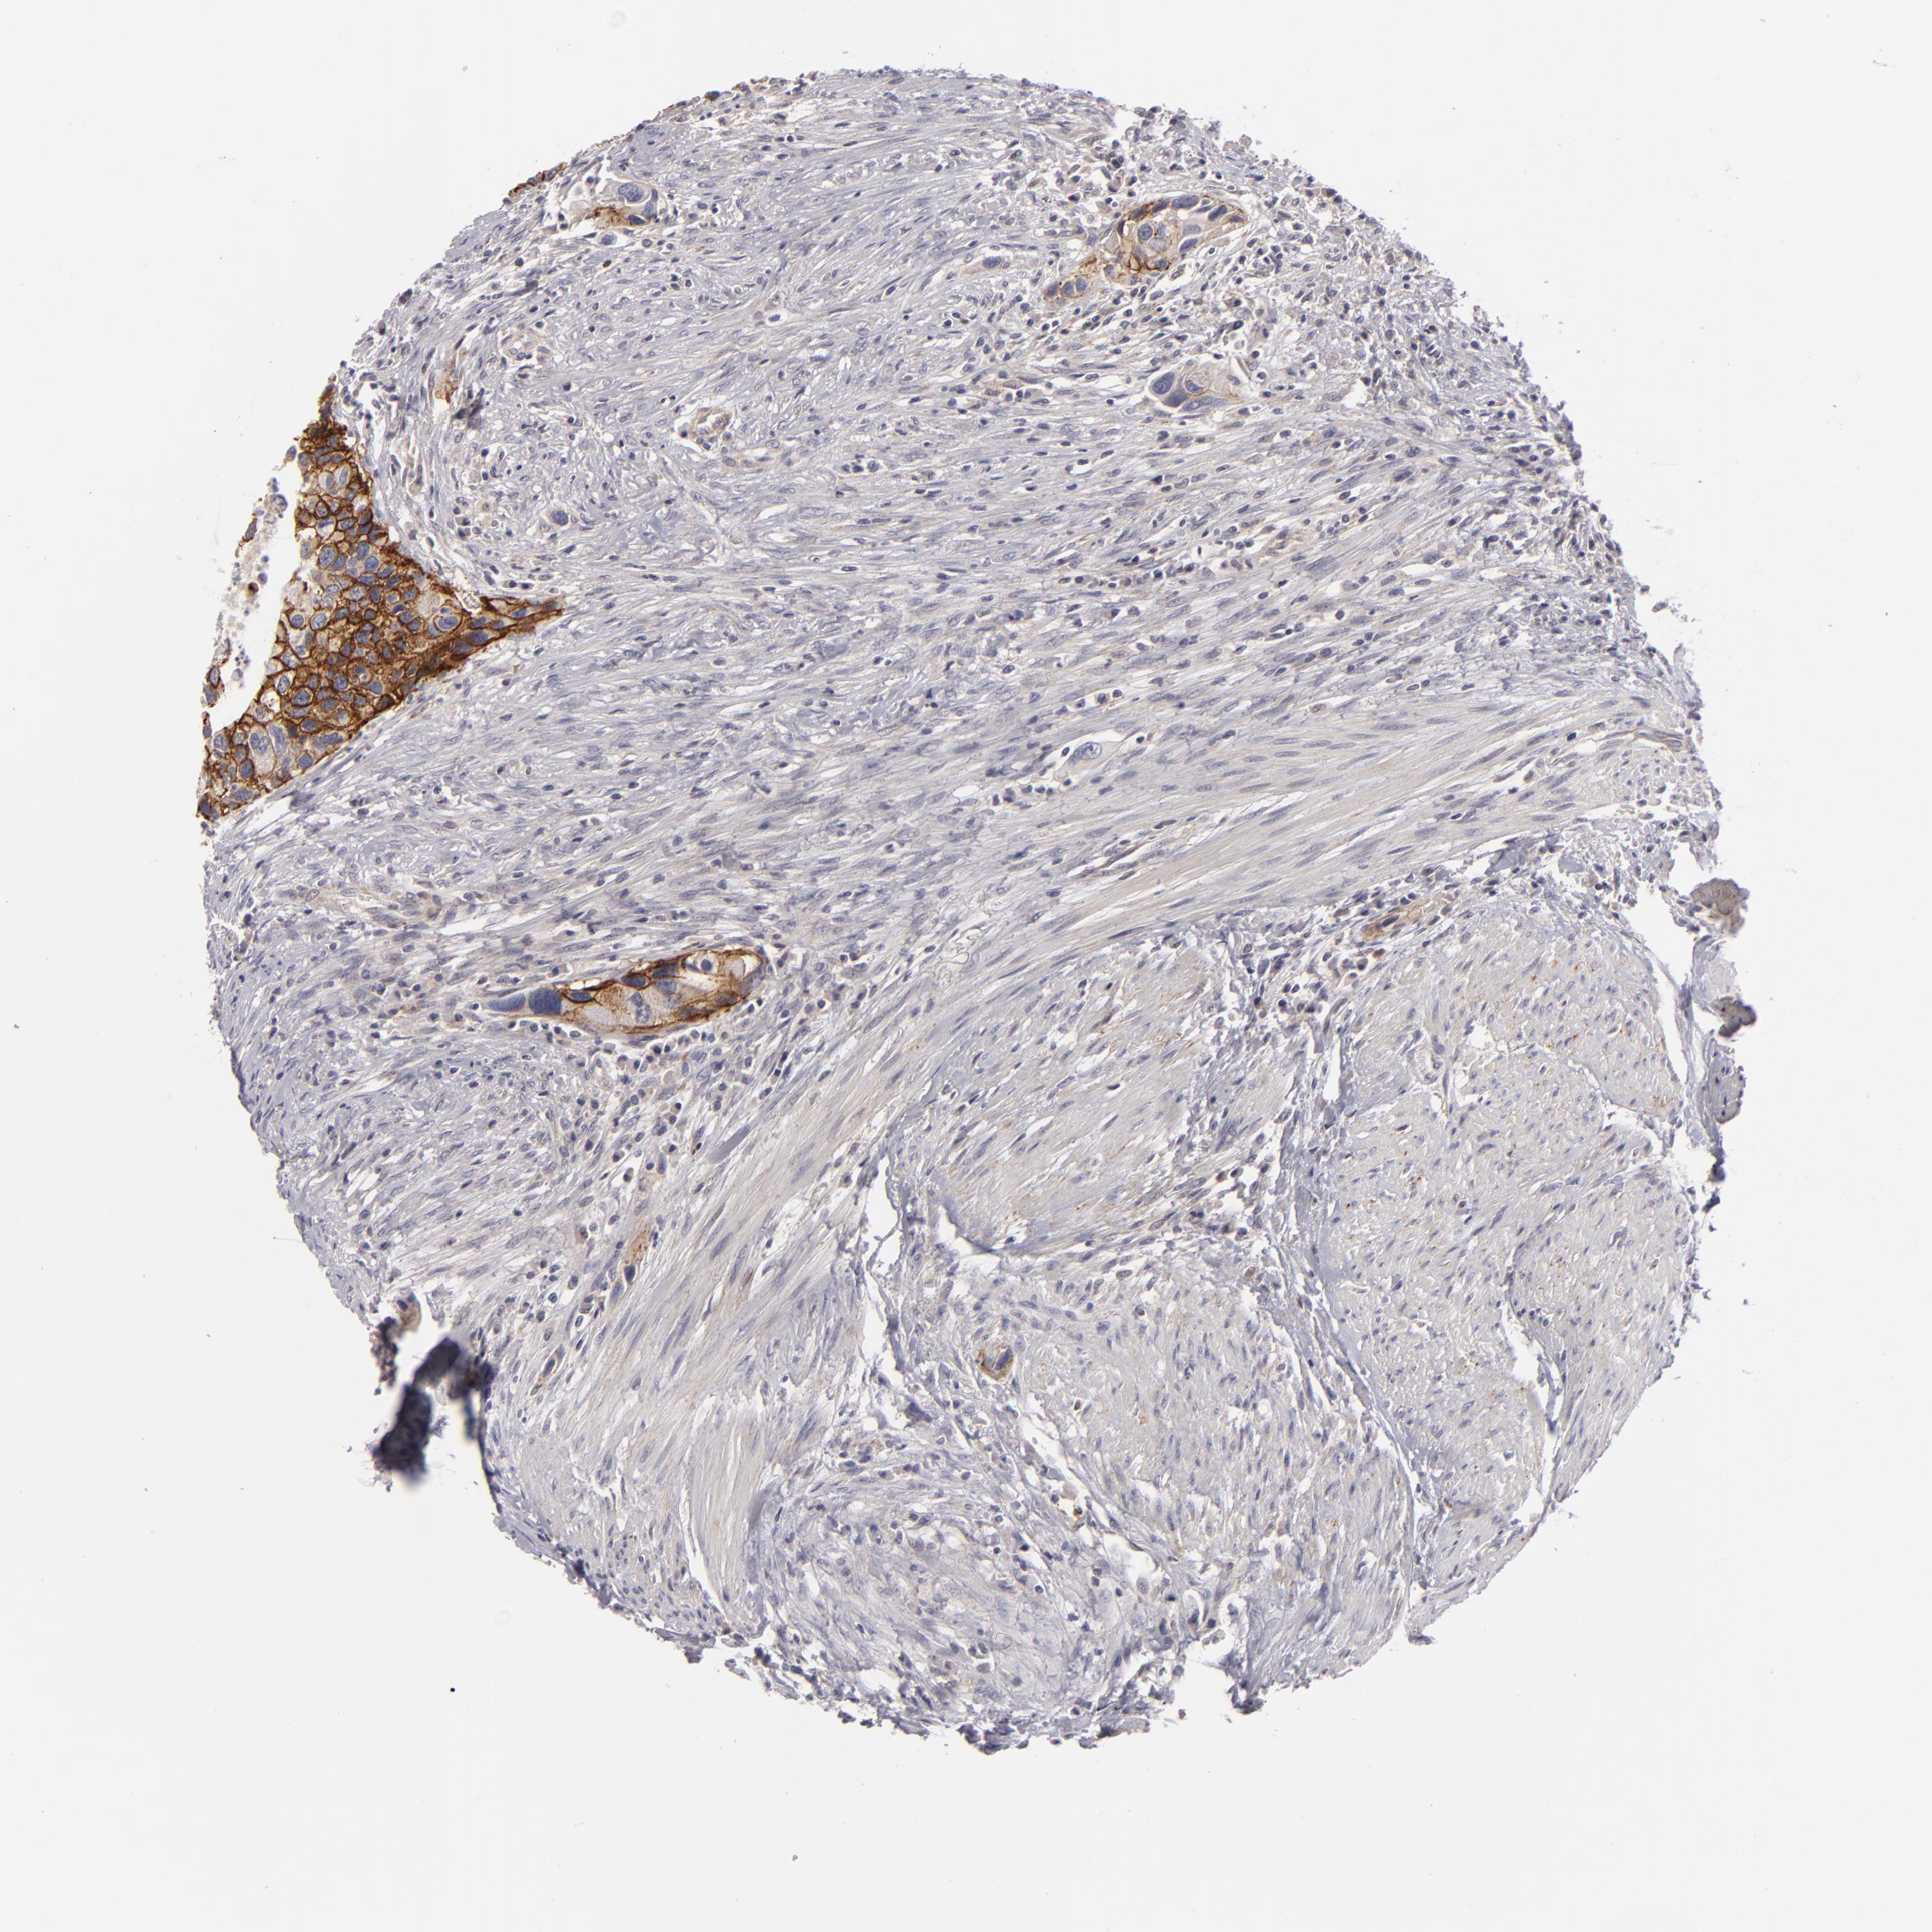

UROTHELIAL CANCER - Protein expressioni

A mouse-over function shows sample information and annotation data. Click on an image to view it in a full screen mode. Samples can be filtered based on level of antibody staining by selecting one or several of the following categories: high, medium, low and not detected. The assay and annotation is described here.

Note that samples used for immunohistochemistry by the Human Protein Atlas do not correspond to samples in the TCGA dataset.

Antibody stainingi

Antibody staining in the annotated cell types in the current human tissue is reported as not detected, low, medium, or high, based on conventional immunohistochemistry profiling in selected tissues. This score is based on the combination of the staining intensity and fraction of stained cells.

Each image is clickable and will lead to virtual microscopy that enables deeper exploration of all samples and also displays staining intensity scores, fraction scores and subcellular localization as well as patient and tissue information for each sample.

Antibody HPA010926

Antibody CAB002148

Urothelial carcinoma, Low grade

Urothelial carcinoma, High grade

Adenocarcinoma, NOS